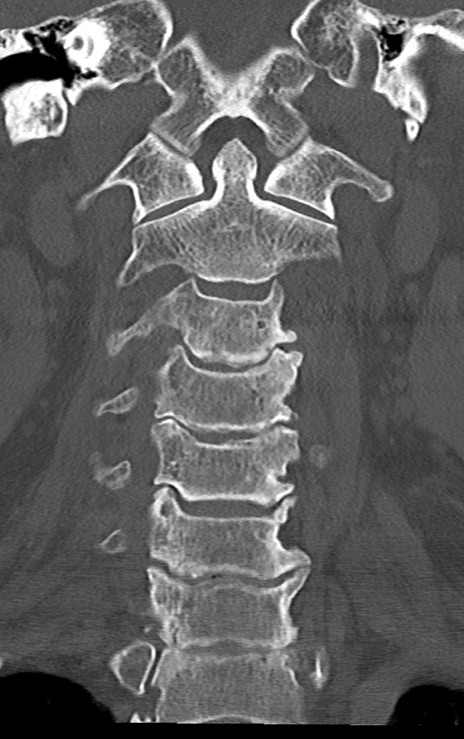

頚椎CT

矢状断像